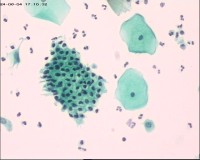

性别

女

年龄

50岁

一般病史

宫颈肥大

标本类型

TCT

制片方法

液基细胞

染色方法

巴氏染色

图1

图2

图3

NILM